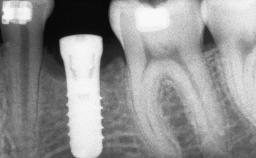

A 56-year-old woman presented for treatment with complete edentulism of the maxilla. She had been using a complete removable denture since she was relatively young (age 30). Her chief complaint at presentation was lack of retention of the upper denture and a desire for a better restoration in order to improve retention, function, and esthetics. An initial clinical examination showed that the anterior maxilla was moderately atrophic both horizontally and vertically, also revealing a vertical deficiency of the posterior alveolar process. The mandible included natural teeth from 45 to 35, with previous extrusion of the anterior teeth that was being orthodontically treated. Also, there were two external hexagon dental implants at sites 46 and 36 that had been inserted elsewhere at a previous point in time. As the conditions in the mandible were healthy, including the teeth and the two implants, the patient had no complaints there.